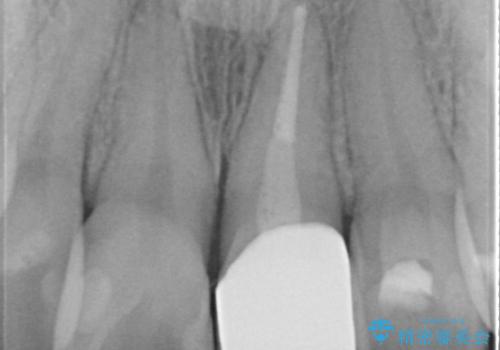

- 矯正前に仮歯にしていた前歯を矯正治療終了後にセラミックによる治療を希望された患者様です。

プラスチックのものから綺麗なセラミックになり喜んでいただきました。